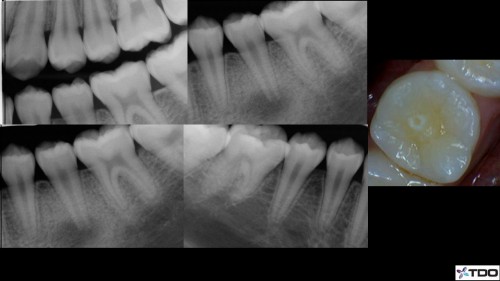

#31 – C shaped Anatomy – Separated file

1st Visit Exploratory access to assess prognosis to confirm restorability and rule out fracture 2nd […]